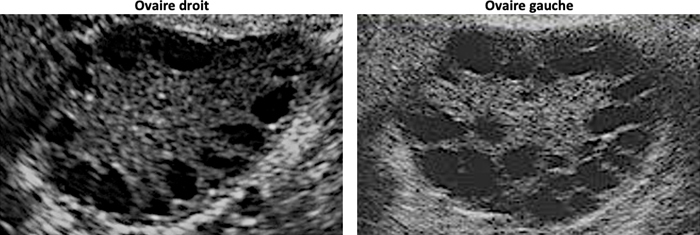

– testostérone : recherche d’une tumeur surrénale ou d’un syndrome des ovaires polykystiques (SOPK).